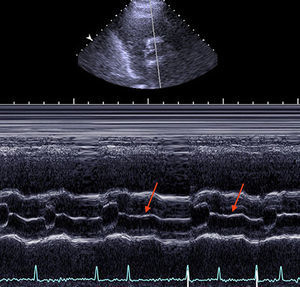

A 70-year-old man presented to the emergency department of our hospital with acute heart failure in the context of atrial fibrillation with rapid ventricular response (Figure 1). Physical examination revealed an irregular pulse, with moist rales in lung fields and lower extremity edema. In addition, a simultaneous electrocardiographic recording disclosed the absence of heart sounds during short diastoles. This finding of “silent” heartbeats led us to perform an echocardiogram, which revealed a left ventricular ejection fraction dependent on the R-R interval, which was normal during long diastoles and showed severe systolic dysfunction during short diastoles. M-mode recording of the mitral and aortic valves was carried out to acquire short-axis images from the parasternal window; they disclosed the failure of the mitral valve to open during short R-R intervals (Figure 2, arrow), as well as the failure of the aortic valve to open during the beat that followed (Figure 3, arrows).

To the best of our knowledge, there have been no previous reports of the presence of isovolumetric beats. Indeed, a reduction in diastole during short cardiac cycles has been documented in patients with atrial fibrillation. The present case report describes this phenomenon in what is probably its most extreme form, with the absence of ventricular filling and failure of the mitral valve to open during very short cardiac cycles. Likewise, the systole following the absence of ventricular filling was ineffective in mechanical terms, as shown by the failure of the aortic valve to open. This unusual echocardiographic finding is clinically relevant as it demonstrates that cardiac auscultation can underestimate the heart rate of patients with atrial fibrillation.